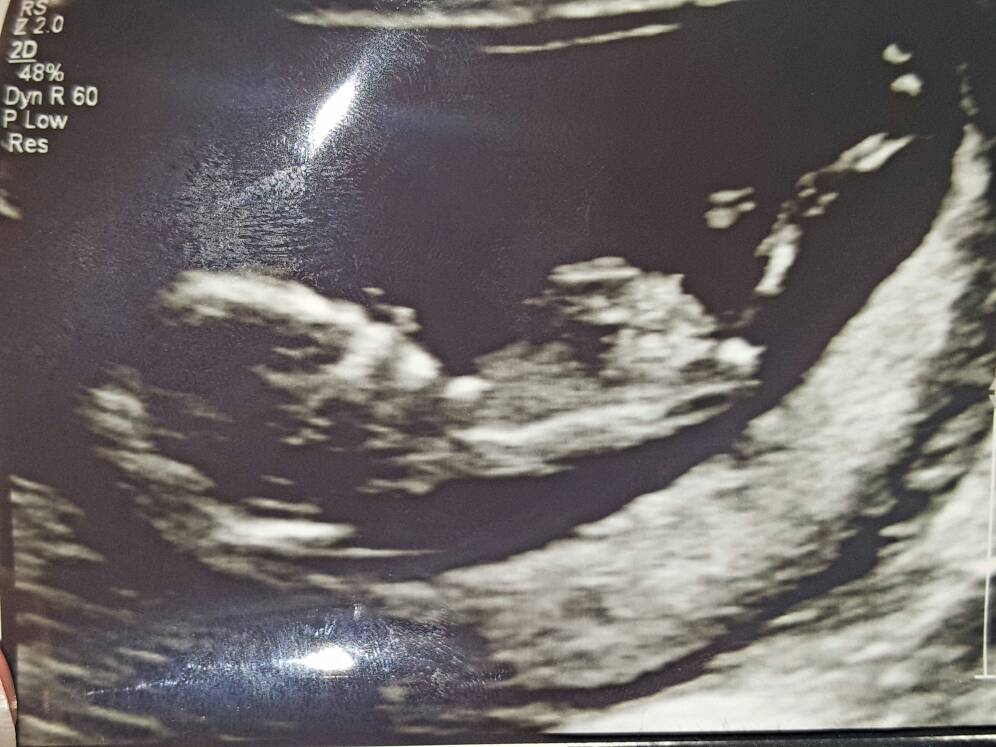

Hi everyone, based on this photos can anyone guess what gender by skull theory. Attachment 34093Attachment 34094Attachment 34095